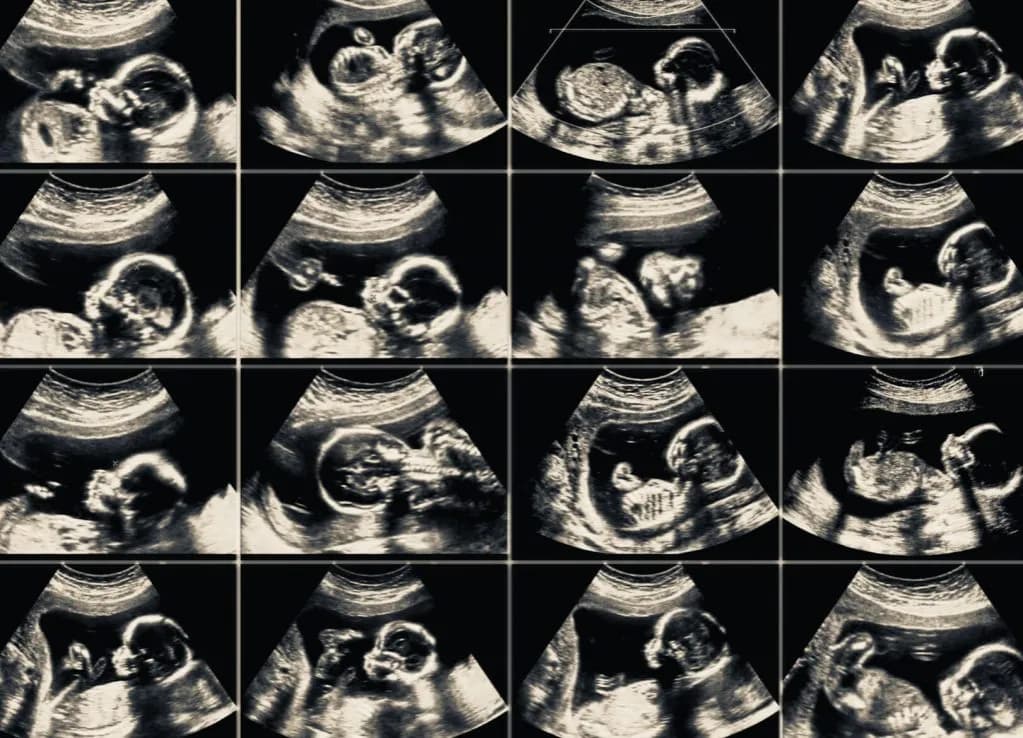

- USG połówkowe powinno być wykonane między 18. a 22. tygodniem, aby ocenić rozwój płodu i wykryć wady wrodzone.

Warto podkreślić, że USG w ciąży, a zwłaszcza USG połówkowe, jest jednym z najważniejszych badań w tym okresie. To badanie, przeprowadzane między 18. a 22. tygodniem ciąży, pozwala na szczegółową ocenę narządów płodu oraz wykrycie ewentualnych wad wrodzonych. Dzięki temu lekarz może ocenić obwód główki, brzucha oraz długość kości udowej płodu, co jest kluczowe dla oceny jego rozwoju.

- Wykrycie wad wrodzonych, takich jak zespół Downa.

- Ocena prawidłowego rozwoju narządów.

- Monitorowanie wzrostu płodu i jego parametrów.

- Określenie ilości płynu owodniowego.

- USG połówkowe – między 18. a 22. tygodniem.

Ważne jest, aby pamiętać o harmonogramie badań, którego przestrzeganie przyczynia się do lepszego zrozumienia stanu zdrowia matki oraz płodu. Na przykład, wykonanie USG połówkowego między 18. a 22. tygodniem ciąży pozwala na szczegółową ocenę narządów płodu i potencjalnych wad wrodzonych, co może być kluczowe dla dalszej opieki. Ostatecznie, podejmowanie odpowiednich kroków w odpowiednim czasie, związanych z badań biochemicznych i inwazyjnych, przekłada się na świadome decyzje dotyczące zdrowia rodziny.